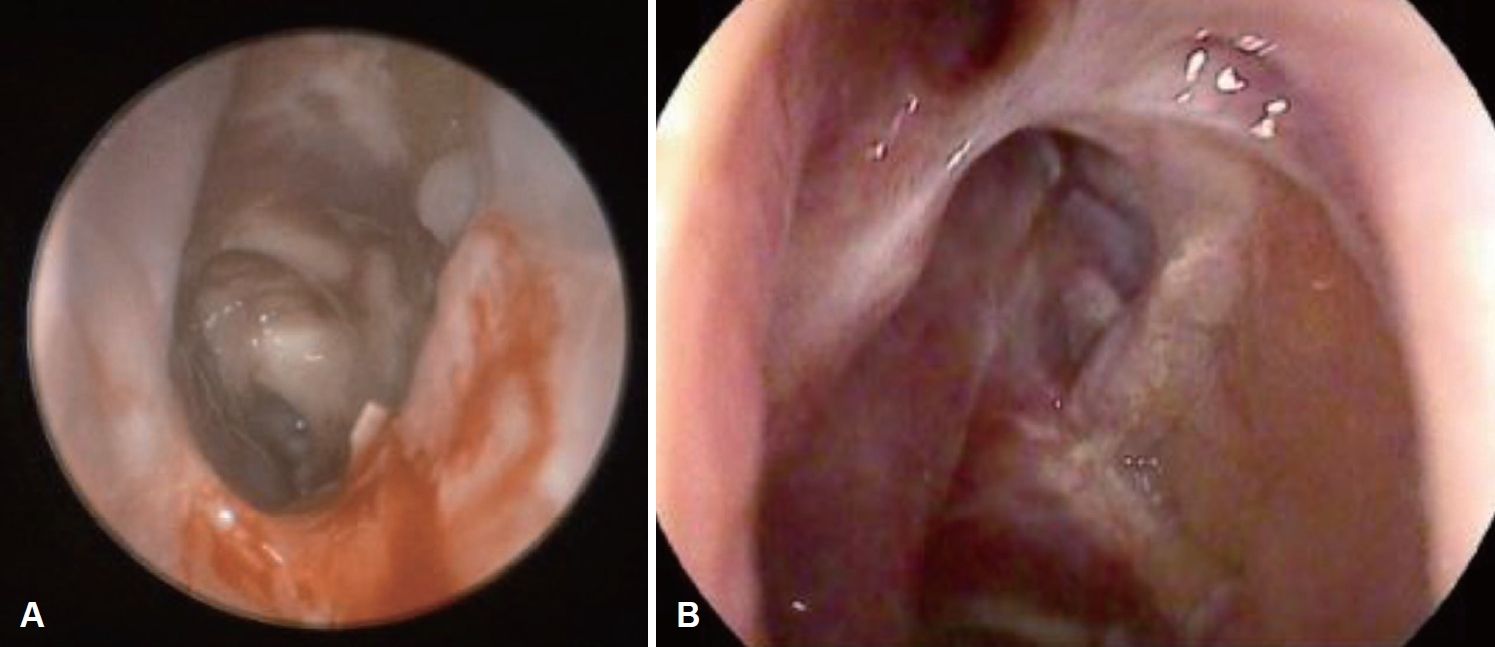

Both middle meatal antrostomy, left anterior, and posterior ethmoidectomy were performed. Fungal balls were identified in the left ethmoid sinus, followed by biopsy and culture. Severe mucosal swelling and mucoprulent rhinorrhea were observed by sinus endoscope in the operative findings, and the department of infectious medicine consultation was performed for using an antifungal agent for orbital complications. (1-3)-β-D-glucan test resulted positive. Aspergillus infestation was confirmed by biopsy, and voriconazole was used after transfer to the department of infectious medicine. The patient gradually recovered visual disturbance after surgery. In the visual field exam, a recovery was observed from 12% to 43% (Fig. 2).

Therefore, in accordance with the NMOSD diagnostic criteria, the patient was scheduled to be transferred to the neurology department after completion of treatment for sinusitis, and the neurology is considering implementing immunosuppressant treatment. After discharge, follow-up every 2 weeks was also performed in the otorhinolaryngology department outpatient department. Endoscopic findings showed that the ethmoid sinus mucosa was recovering well without any specific findings (Fig. 4).

NotesAuthor Contribution Conceptualization: Jun-Won Seo, Ji Yun Cho. Data curation: all authors. Formal analysis: all authors. Investigation: all authors. Methodology: Jun-Won Seo, Ji Yun Cho. Project administration: Ji Yun Cho. Resources: Jun-Won Seo, Ji Yun Cho. Software: all authors. Supervision: Ji Yun Cho. Validation: all authors. Visualization: Do Yoon Jeong, Hyejeen Kim. Writing—original draft: all authors. Writing—review & editing: Ji Yun Cho. Fig. 1.Radiology findings. A: Axial view of orbit MRI showed T2 low signal intensity lesion in the left ethmoid sinus, mild engorgement of left cavernous sinus and mild enhancement of left orbit. B: Axial view of enhanced PNS CT showed inhomogeneous enhancement with mucosa thickening in left ethmoid sinus with calcifications and mild enhancing left cavernous sinus. C: Coronal view of non-enhanced PNS CT showed soft tissue density filled in the left ethmoid sinus with calcifications. PNS, paranasal sinus. Fig. 2.Visual field examinations. A: Preoperative visual field exam showed left visual disturbance as low visual field index (VFI: 12%). B: Postoperative visual field exam showed improved left visual disturbance as increased visual field index (VFI: 43%). VFI, visual field index. REFERENCES1. Holroyd KB, Manzano GS, Levy M. Update on neuromyelitis optica spectrum disorder. Curr Opin Ophthalmol 2020;31(6):462-8.